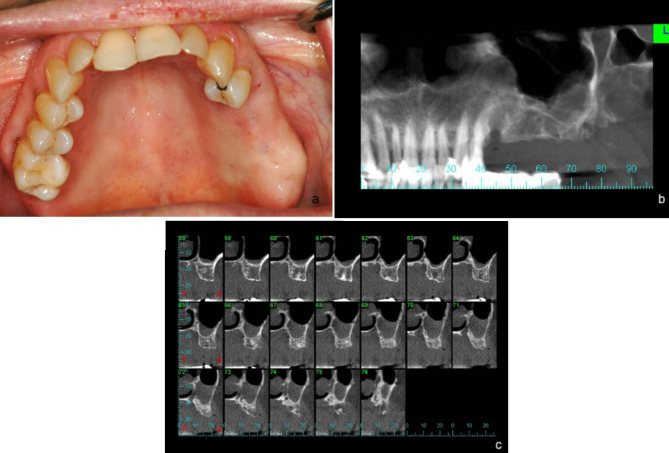

Objectives: Perforation of the Schneiderian membrane (SM) is a common intraoperative complication of sinus augmentation. This study aimed to evaluate risk factors for SM perforation, and to compare clinical outcomes between patients with SM perforation repaired using crosslinked collagen membranes (CLM) compared to those with an intact SM.

Methods: A retrospective cohort study was conducted at a single tertiary medical center. Data was collected on patients requiring sinus augmentation via lateral approach prior to implant placement. The collected data included demographics, surgical details, implant outcomes, radiographic analysis, and presence of SM perforation. In cases of perforation a CLM was used to repair the SM. Statistical analysis was performed to evaluate risk factors for perforation and whether SM perforation repair using CLM influenced early implant failure (EIF). A p-value < 0.05 was considered significant.

Results: Data on 194 individuals who underwent 278 lateral approach sinus augmentation procedures was collected. SM perforation occurred in 66 (23.74%) sinuses. Treatment of SM perforation using CLM yielded similar results to sinuses without perforations: EIF and the augmented gained bone did not correlate with SM perforation. Younger patients, and thick SMs (> 3 mm) had significantly lower risk of perforation.

Conclusions: Older age and thinner SMs are risk factors for sinus membrane perforations. No significant differences in bone gain and EIF were found between perforated and intact membranes.

Clinical relevance: Schneiderian membrane perforation repair using crosslinked collagen membrane provides comparable results to sinus augmentations without perforations, demonstrating its effectiveness in preventing complications.